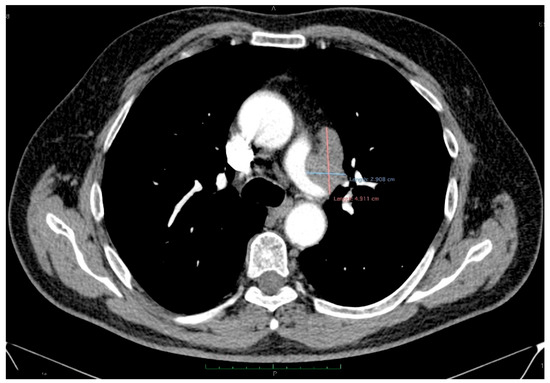

Synchronous Pulmonary and Cecal High-Grade Neuroendocrine Carcinomas Presenting as Hepatic Metastases: A Diagnostic Challenges and Literature Review

Background and Clinical Significance: Neuroendocrine neoplasms (NENs) are a group of malignancies that may remain clinically silent for many years. The presence of hepatic metastases can be the first clue leading to diagnosis. Case Presentation: We report the case of a 67-year-old man [...] Read more.

Background and Clinical Significance: Neuroendocrine neoplasms (NENs) are a group of malignancies that may remain clinically silent for many years. The presence of hepatic metastases can be the first clue leading to diagnosis. Case Presentation: We report the case of a 67-year-old man with intermittent tiredness and suspicious hepatic nodules detected on routine abdominal ultrasound. Contrast-enhanced ultrasonography showed arterial hyperenhancement with early washout, suggestive of metastases. Synchronous high-grade neuroendocrine carcinomas (NECs) of the lung and cecum were identified. Although the liver lesions were initially presumed to arise from the cecal tumor, liver biopsy immunohistochemistry was TTF-1 positive/CDX2 negative, whereas the cecal lesion was TTF-1 negative/CDX2 positive. This mutually exclusive immunophenotype confirmed two separate primary carcinomas. Given the high-grade histology, the patient received platinum-based chemotherapy and achieved a partial response. Conclusions: This case illustrates the diagnostic complexity of synchronous lesions and highlights the “mirage of the first lesion” phenomenon, in which the initially detected tumor may not represent the true primary site. A comprehensive, multidisciplinary strategy is crucial for establishing the correct diagnosis and guiding optimal management. Full article

(This article belongs to the Special Issue Diagnosis and Management of Neuroendocrine Tumors)